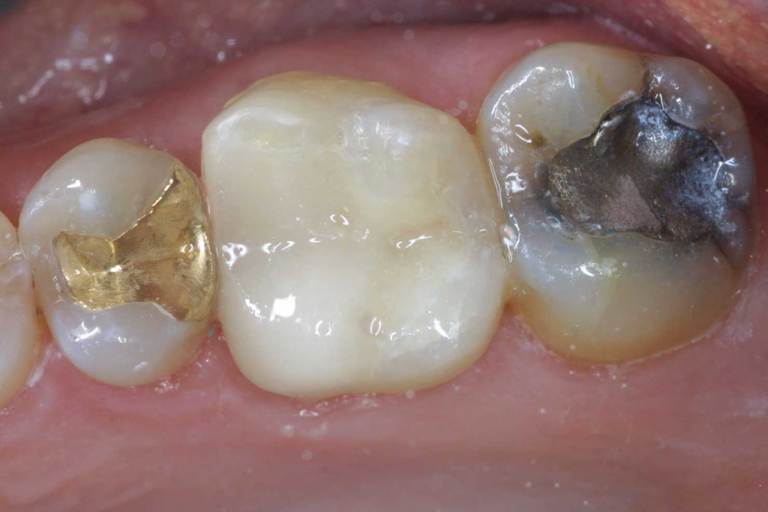

Replacing Old Silver Or Gold Amalgam Fillings

John W. Schulz, D.D.S. specializes in beautiful cosmetic dentistry. Metal fillings are often thought of as an eyesore especially with the front teeth that are visible to everyone when you smile. We are able to remove those old metal fillings and replace them with today's white fillings which are nearly identical in color to the teeth that they are in.

Composite fillings are today's modern filling choice. They are made to match your tooth's natural color to make them virtually invisible to notice and are placed onto the tooth by bonding the filling material to the tooth so they do not have the unlikely chance of falling off. Many patients choose to replace their old silver and gold fillings with composite fillings.

White fillings are made from a high-strength composite resin that can be easily color-matched to your natural tooth making it nearly invisible to you and anyone else. Unlike silver and gold fillings, composite tooth-colored fillings actually bond to the tooth which means they support the surrounding tooth structure, which helps to prevent breakage and insulate the tooth from excessive temperature changes. You are much less likely to have a composite filling fall out which is a common issue with metal fillings.